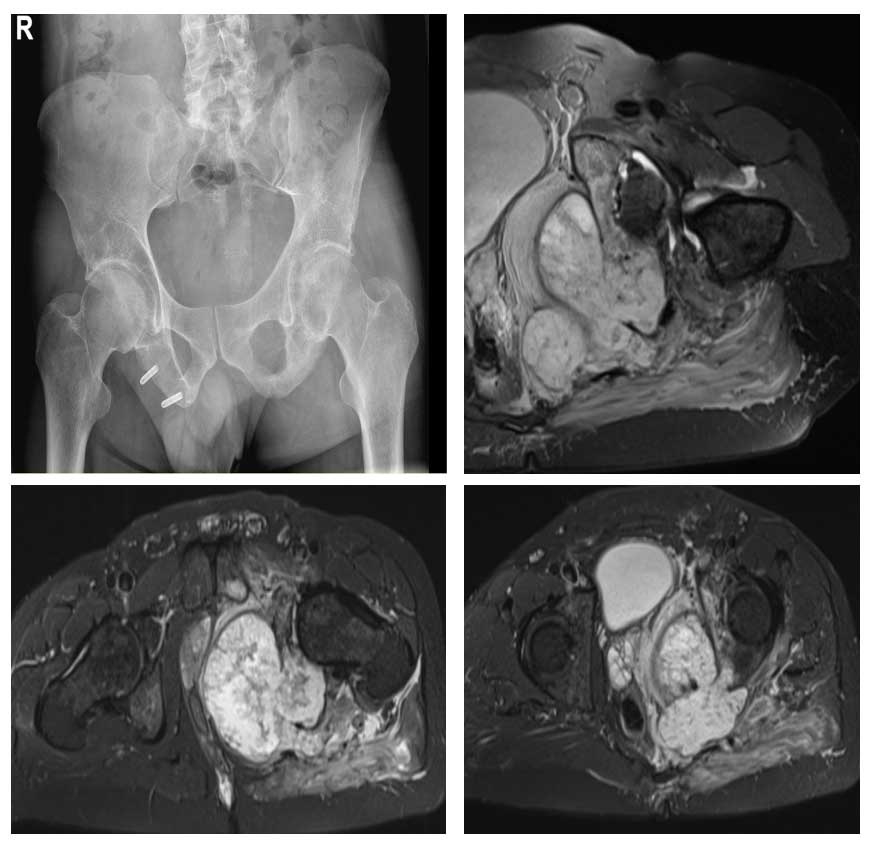

Ameliyat Öncesi: Röntgende sol asetabulumda düzensizlik, MR’da kemikte yıkıma neden olan büyük boyutta tümör dokusu görülmekte.